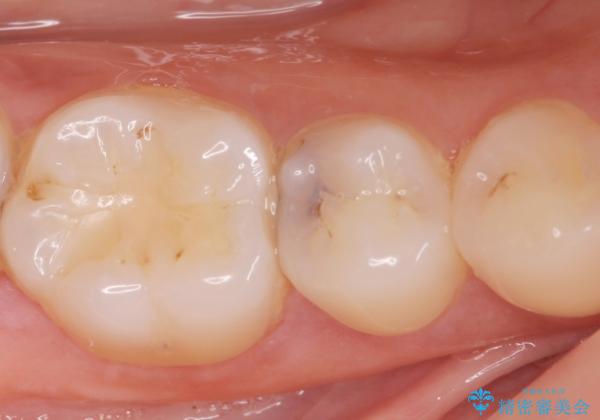

[e-maxインレー] 矯正治療前の虫歯治療

- 矯正治療前の患者様です。

う蝕があったのでe-maxインレーにて治療しました。

- e-maxインレー 7.7万円 費用は治療当時の料金となります

う蝕があるままで矯正を始めてしまうと矯正治療中にう蝕が悪化する可能性があります。矯正治療を行う前はう蝕や歯周病がある場合にはしっかり治療を行なってから矯正治療がスタートします。

![[e-maxインレー] 矯正治療前の虫歯治療の治療中](https://seimitsushinbi.jp/wp/wp-content/uploads/2023/08/IMG_2859-1-500x350.jpg?v=1691812264)